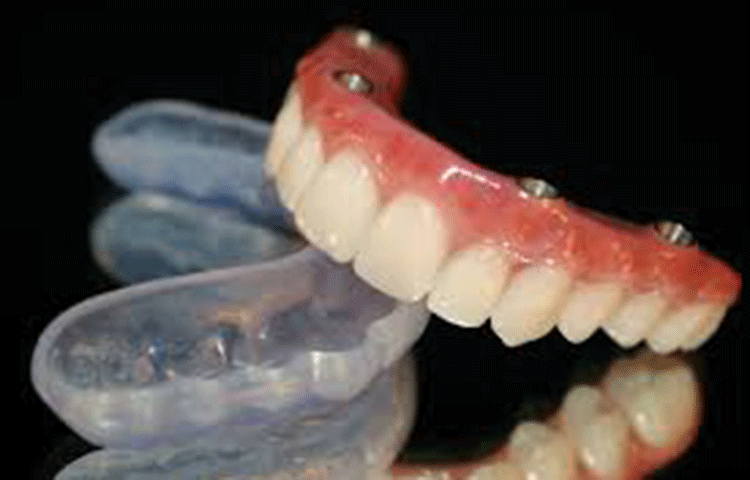

サージカルガイドの使用

当院のインプラント治療でもっとも重視しているのは安全性です。

インプラントを入れる位置により、その後の持ち具合にまで影響してきます。

難症例には手術用マウスピースを用いて、安全にインプラントの計画、埋入を行います。